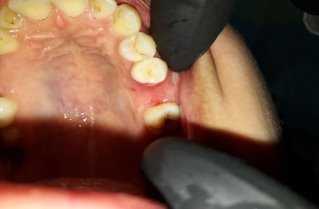

Пластику мягких тканей под зоной перфорации проводили следующим образом: под местным обезболиванием (инфильтрационная и проводниковая анестезия) отслаиваются слизистая оболочка с надкостницей с небный стороны до соответствующего размера дефекта. Затем отслойку расщепляем поперечным разрезом, отделяющую слизисто-надкостничную отслойку на два слоя:

наружную — слизистая оболочка с верхними слоями эпителия

внутреннюю — надкостница с нижними слоями слизистой оболочки.

Внутренний — нижний слой эпителия с надкостницей разрезается по бокам, образуя лоскут на ножке, и тянется к дефекту и зашивается к краям дефекта. Наружный — верхний слой эпителия остается на месте, чтобы закрыть раневую поверхность на небе, выполняя роль биологической повязки.

Техника пластики проводилась таким же путем как описано выше. (рис 2)